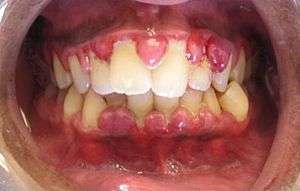

A case of gingivitis | |

Gingivitis ("inflammation of the gum tissue") is a non-destructive disease that occurs around the teeth.[1] The most common form of gingivitis, and the most common form of periodontal disease overall, is in response to bacterial biofilms (also called plaque) that is attached to tooth surfaces, termed plaque-induced gingivitis.

The symptoms of gingivitis are somewhat non-specific and manifest in the gum tissue as the classic signs of inflammation:

- Swollen gums

- Bright red or purple gums

- Gums that are tender or painful to the touch

- Bleeding gums or bleeding after brushing and/or flossing

- Bad breath (halitosis)

Additionally, the stippling that normally exists on the gum tissue of some individuals will often disappear and the gums may appear shiny when the gum tissue becomes swollen and stretched over the inflamed underlying connective tissue. The accumulation may also emit an unpleasant odor. When the gingiva are swollen, the epithelial lining of the gingival crevice becomes ulcerated and the gums will bleed more easily with even gentle brushing, and especially when flossing.